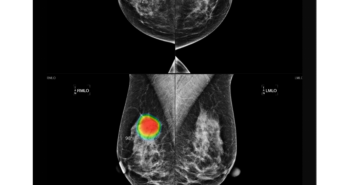

의료 인공지능(AI) 기업 루닛이 지난해 11월 운영권을 수주한 호주 뉴사우스웨일스(New South Wales, 이하 NSW) 주정부의 국가 유방암 검진 프로그램 ‘BreastScreen NSW(이하 BSNSW)’ 사업의 첫 단계를 성공적으로 종료하고, 2단계에 공식 착수했다. BSNSW는 국가 단위의 암 검진 사업에서 AI 솔루션을 도입한 전 세계 최초의 사례로, 시드니를 주도로 하는 NSW 주정부는 이 프로젝트를 통해 해당 주에 거주하는 40세 이상 모든 여성에게 무료 유방암 검진을 제공하고 있다. 루닛은 전체 3단계의 프로젝트 과정 중 1단계에서 약 65만 건의 유방촬영 영상을 AI 영상분석 솔루션 ‘루닛 인사이트 MMG’로 분석, 기술의 정확성과 신뢰성을 입증했다. 이번 2단계에서는 검진 데이터 약 20만 건을 활용해 내년 6월까지 약 6개월 간 추가 검증이 진행된다. 2단계는 실제 설치에 앞서 루닛 솔루션의 최적화 및 유효성 검증 작업(Prospective Validation)을 진행하며, 이 과정에서 최근 미국 식품의약국(FDA)의 승인을 받은 3차원 유방단층촬영술 AI 영상분석 솔루션 ‘루닛 인사이트 DBT’에 대한 평가 작업도 진행될 예정이다. 이후 마지막 3단계에서는 BSNSW 의료진이 루닛 인사이트 MMG를 활용해 검진을 수행할 예정이다. 서범석 루닛 대표는 “루닛이 전 세계 최초로 국가 단위 유방암 검진 프로그램에 채택된 것은 단순한 기술적 성과를 넘어서는 의미를 갖고 있다”며 “이번 프로젝트는 유방암 진단 분야에서 AI의 중요한 역할을 조명하는 사례가 될 것이며, 앞으로 공공의료 시장에서 암 검진의 새로운 기준을 제시하는 발판이 될 것으로 기대한다”고 말했다. 관련 기사 더보기 https://www.venturesquare.net/904960